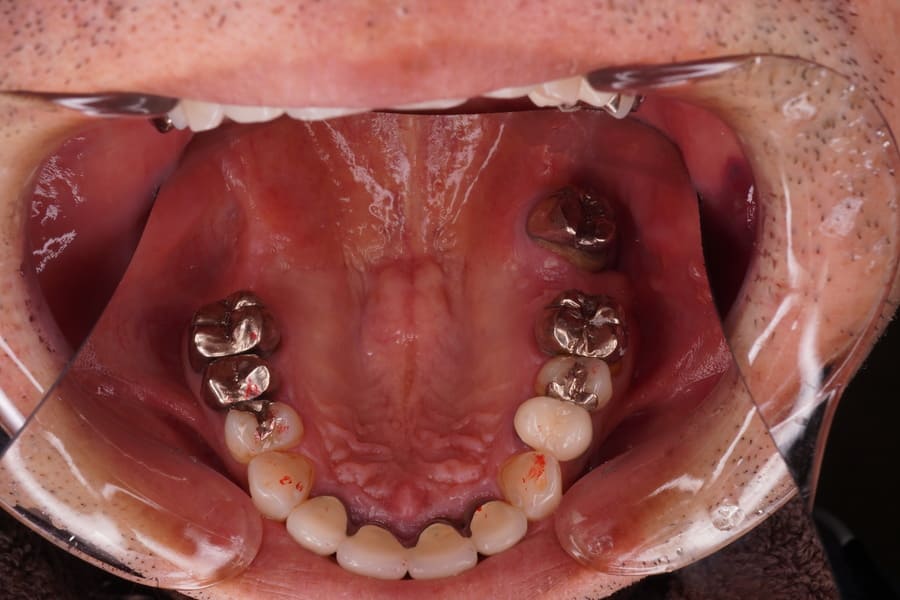

【症例概要】左上7番欠損。欠損放置後にノンメタルクラスプデンチャーを装着することにより審美的・機能的改善を図った症

Before

左上7番欠損。 昔、入れ歯を作ったが近年使用していない。 歯周組織は最大ポケット3㎜でエックス線所見においても問題となる骨欠損は認められず左上6,8番ともブリッジ、義歯の支台歯として適応可能と判断した。 補綴装置としてブリッジ、義歯、インプラントいずれも適応可能であった。 患者さんの希望は、補綴物や骨を出来るだけ傷つけない治し方であった。 各種補綴方法の利点・欠点・特徴・金額を説明した後、 患者さんの希望として、出来るだけ違和感がない物、見た目もあまり金属等で目立たないもの、落としても壊れにくい物であった。 これらのことを総合的に検討して、ノンメタルクラスプデンチャーの適応を提案し了解が得られたので製作することとした。 各種あるノンメタルクラスプデンチャーの材料の種類として、比重が軽く生体親和性が高く比較的柔らかいポリプロピレン系を選択した。 理由として一歯欠損のため義歯のたわみが起こりにくいこと、そのことによる適合不良が起こりにくいこと。上顎が対象のため軽めの材料が適していることなどである。 左上6番遠心、8番近心に明瞭なレストシートを設定することとした。 日本補綴歯科学会発行のノンメタルクラスプデンチャーガイドラインにも義歯の安定のためにメタルレストの重要性が述べられている。 まず歯周基本治療を行い歯周組織の安定を図った。 口腔内にて冠の一部を切削・研磨して明瞭な広さ、深さのレストシートを設置した。 ろう義歯試適を行い咬合のずれ等問題がないことを確認した、 患者さんに鏡を見ながら着脱の練習をしていただき、ご自身での取り扱いが可能であることを確認した。 1週間後に来院していただき、各種チェックを行い、粘膜面に痛みがあったため適合検査を行い過圧部分があったため調整を行った。咬合に問題はなかった。 1週間後に痛みが出ていたため2週間後にリコールを行いさらに粘膜面の調整を若干行った。 その後、2週間後にリコールを行い問題がないことを確認した。 ノンメタルクラスプデンチャーによる欠損補綴 |